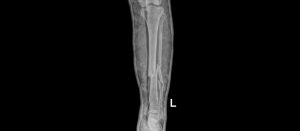

Hình ảnh chụp X-quang xương cẳng chân của bệnh nhân trước và sau phẫu thuật

Sau 1 giờ phẫu thuật dưới hướng dẫn của hệ thống C-arm, kết quả kiểm tra phim chụp X-quang 2 xương cẳng chân của bệnh nhân cho thấy xương nắn chỉnh tốt. Sau mổ 1 ngày bệnh nhân đã giảm đau rõ rệt và đã có thể tập vận động. Sau phẫu thuật 7 ngày, tình hình sức khỏe của bệnh nhân hồi phục tốt và đã được ra viện vào ngày 02/10/2023.